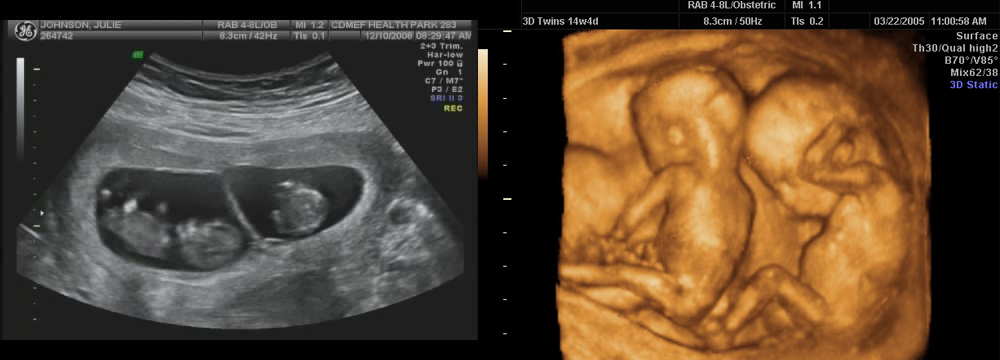

Фотография Плода В Животе

Фотография Плода В Животе 113 фотографий